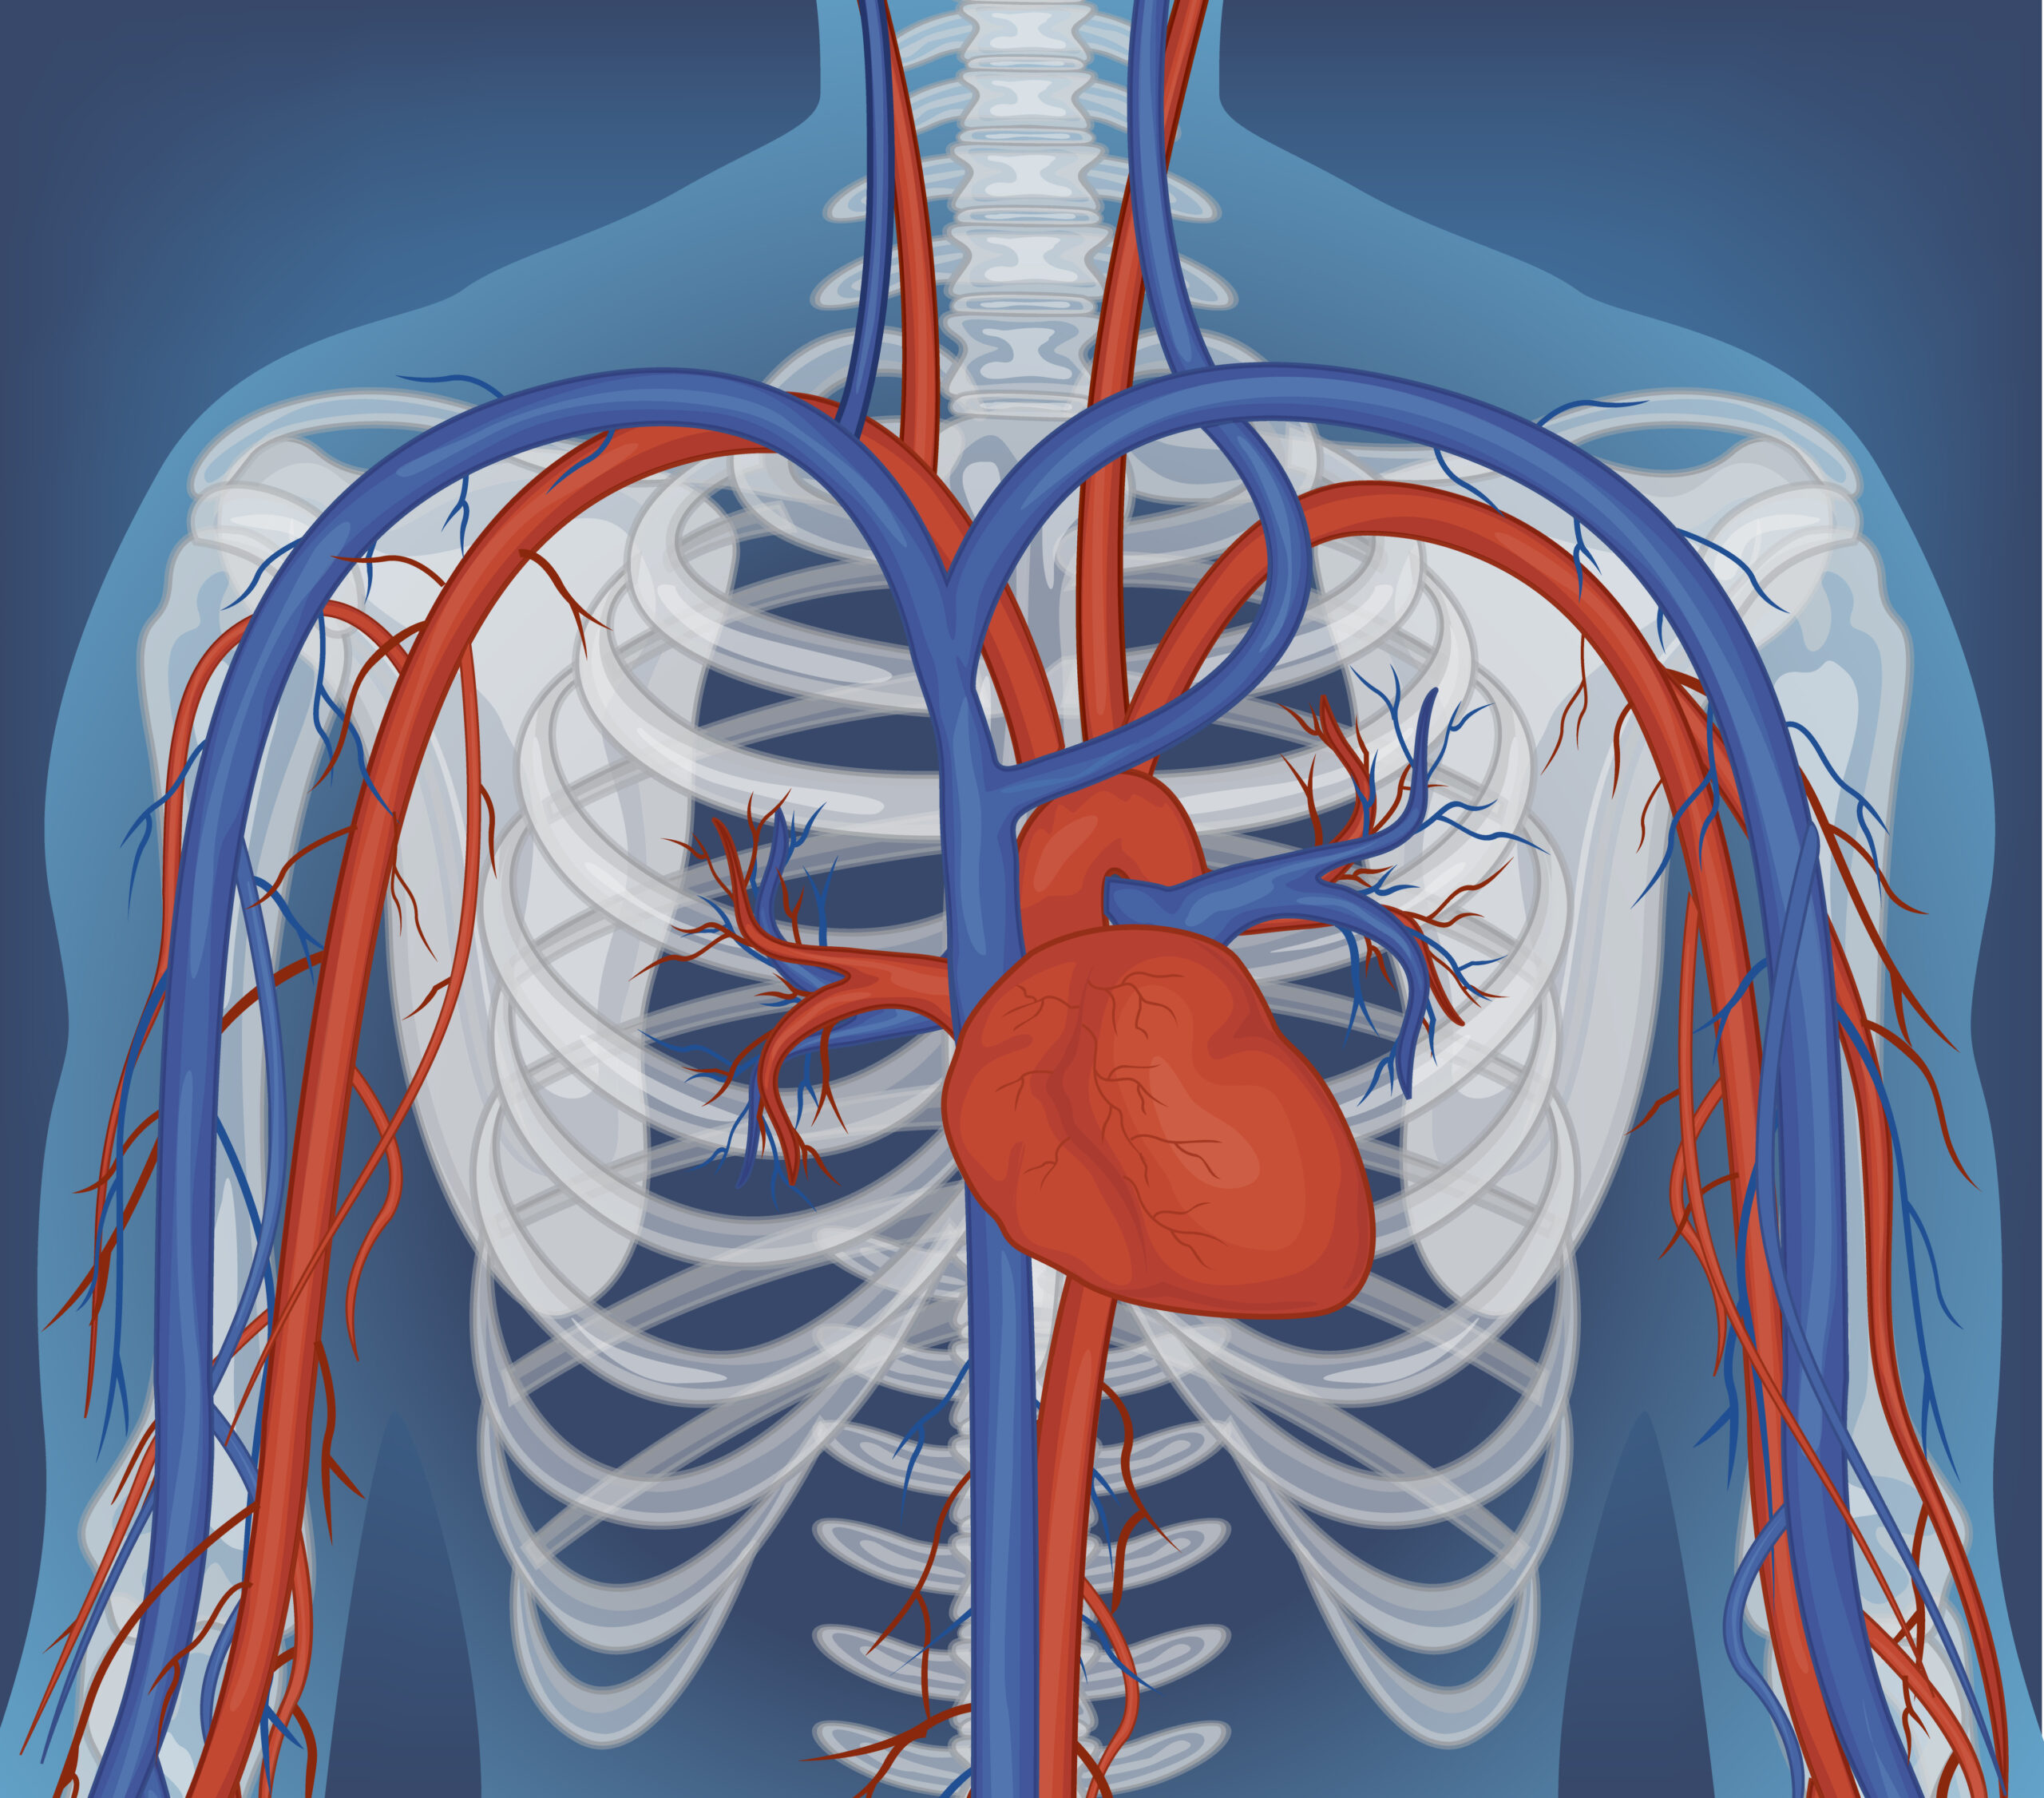

You may have heard that the circulatory system is a flow tube that pumps blood from the heart, through the arteries, making the blood flow, and then back through the veins to the heart. However, the veins do not return blood to the heart by simple passive flow; the skeletal muscle in our bodies is primarily responsible for returning blood from our legs to the heart. To return blood to the heart against the upward pull of gravity, it requires high pressure contractions of muscles surrounding the deep veins. Specifically, the calf muscles have a function of the muscle squeezing the blood in order to pump it up against gravity to the heart. This peripheral pump is essential for the circulatory system to function.

When the calf contracts during walking, running, or any rhythmic lower limb activity, the muscle compresses these deep veins. Venous valves open upward and close downward, so the compressed blood moves toward the heart rather than flowing back down. The National Institutes of Health has published extensive material on the physiology of venous return, and the skeletal muscle pump is consistently described as the dominant mechanism for moving blood out of the legs against gravity (NIH on circulation).

In the healthy adult, the muscles, veins and blood vessels are arranged in a functional system that permits a person to walk for hours each day without developing painful swelling of the lower legs.

The underlying message is that the skeletal muscle pump is not a peripheral detail of lower limb anatomy. It is the primary mechanism by which blood gets back to the heart from the feet and lower legs, and it is structurally dependent on the muscles, joints, and movement patterns that bodyworkers spend their careers studying.

Venous return from the lower limbs is as much a musculoskeletal event as it is a cardiovascular event. The calf muscle pump involves the gastrocnemius and soleus muscles and the ankle joint, and is primarily controlled by muscle contraction. The influence of decreased muscle tone, reduced joint mobility, and aberrant movement habit on lower limb venous return are discussed.